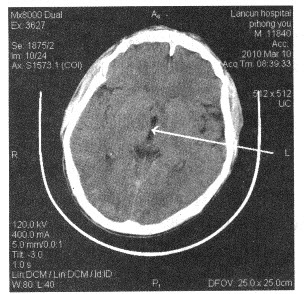

下面颅脑断层图像中箭头所指为()

A:鞍上池

B:大脑外侧窝池

C:第三脑室

D:小脑上池

E:第四脑室